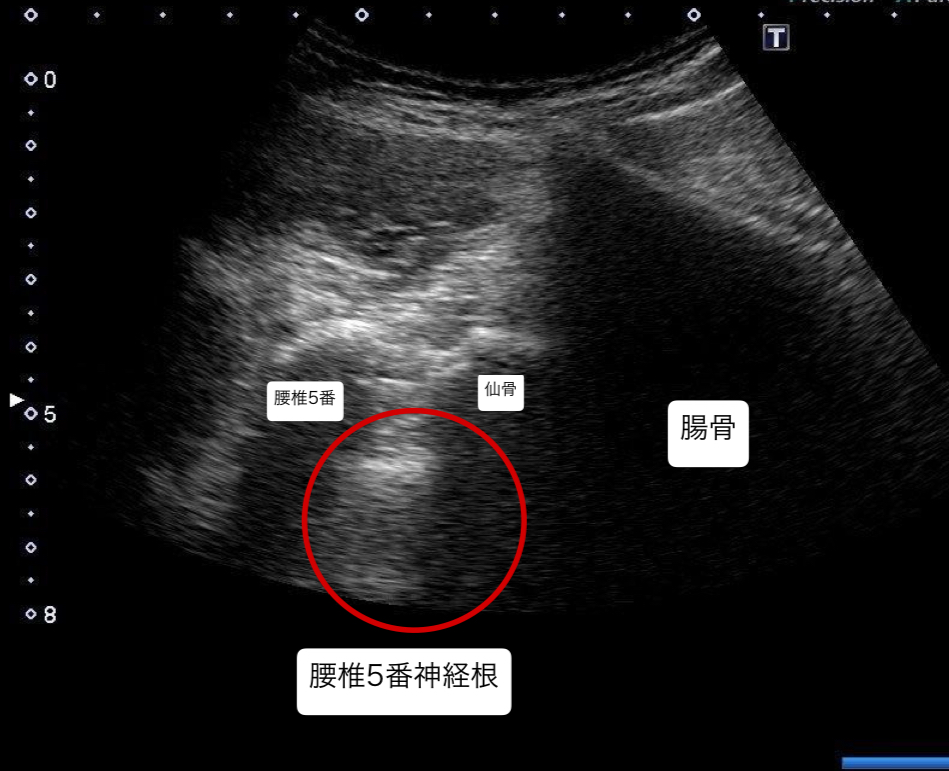

・腰椎5番目神経根と、股関節周囲筋に対し超音波エコーガイド下鍼施術を行った。

超音波エコーガイド下での鍼施術を行い、痛みや痺れが軽減したことから腰椎5番神経根症状だったと考える。同時に、腰椎にかかるストレスの原因が股関節周囲筋の柔軟性低下であったと考える。